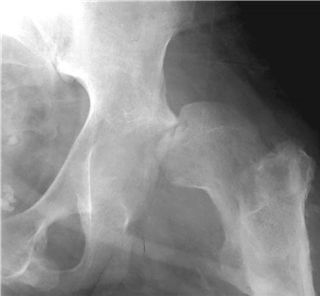

A 77-year-old woman fell off her bicycle sustaining this injury.

What does this radiograph show and how would you classify this fracture?

There is a displaced intracapsular fracture of the right neck of femur. I would describe this as a Garden IV fracture as there is complete displacement. Clinically the most important classifi cation is simply between displaced and undisplaced fractures.

What would you like to like to know about the patient?

I need to know about any other injuries and the patientโ€™s acute medical status. I would then enquire about medical co-morbidities, residential status and her pre-morbid mobility. Her mental status both acutely and pre-injury are also important.

What is your initial management?

I would manage this patient along the recent British Orthopaedic Association Standards for Trauma (BOAST) guidelines. She requires analgesia, plain radiographs, and admission to an appropriate ward within 4 h. Routine bloods and electrocardiogram (ECG) are performed and the patient rehydrated. I would plan for surgery within 48 h unless a reversible medical condition was present.

How would you manage this patient?

A s mentioned earlier, I would follow the BOAST guidelines. I would discuss treatment with her and propose a total hip replacement (THR). Studies show that patients do better functionally with THR and re-operation rates are lower. I would certainly expect this particular patient to do better with THR. I would use a cemented cup and stem with a 32 mm head via a modifi ed Hardinge approach.

Although relatively uncommon, it is recommended that an orthogeriatrician should be involved in all phases of this patientโ€™s care.

How would you manage this fracture if it occurred in a 42-year-old?

I would aim to conserve the femoral head by reducing the fracture under direct visualization and fi xing internally with three screws.

This patient presented at 10 p.m. Would you operate that night?

I would operate the next morning as evidence suggests that rapid surgery does not aff ect outcome. The most important factor is accurate reduction.